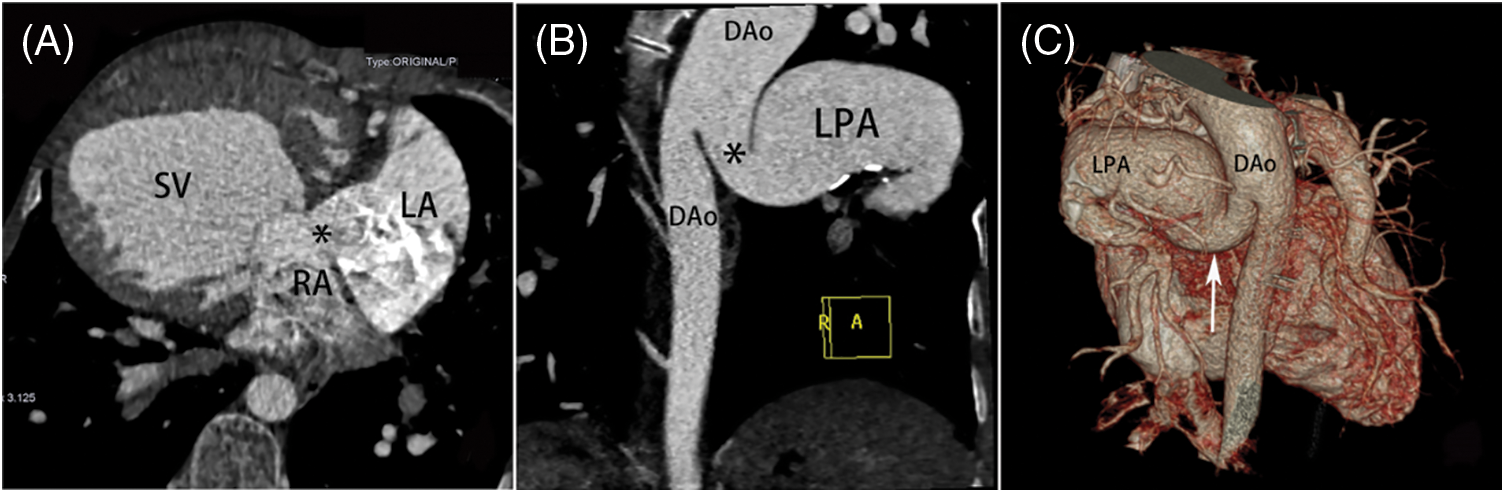

The various intracardiac and extracardiac malformations observed during surgery are detailed in Table 2. In terms of intracardiac malformation, patients with SV are most likely to be associated with atrial septal defect (33/75, 44.0%). In patients with SA, the most common abnormalities were pulmonary artery stenosis (12/24, 50.0%) and pulmonary valve stenosis (10/24, 41.7%) (Fig. 2). In SV patients, the top three malformations were patent ductus arteriosus (25/75, 33.3%), pulmonary artery stenosis (23/75, 30.7%) and right ventricular double outlet (20/75, 26.7%) (Fig. 3). In the patients with SA-SV, the incidence of pulmonary artery dilation (11/24, 45.8%), right aortic arch (10/24, 41.7%), right ventricular outflow tract stenosis (9/24, 37.5%), coarctation of aorta (9/24, 37.5%) were more pronounced (Fig. 4).

Figure 3: SV in a male aged 13 years. (A) The transverse plane of a SV with atrial septal defect (*) and dextrocardia. (B) (C) MPR and VR images show that the DAo communicates with the LPA (*) (white arrow). VR image shows that the left pulmonary artery sends out many small branches. LA = left atrium, MPR = multiple planar reconstruction, other abbreviations as in Figs. 1 and 2